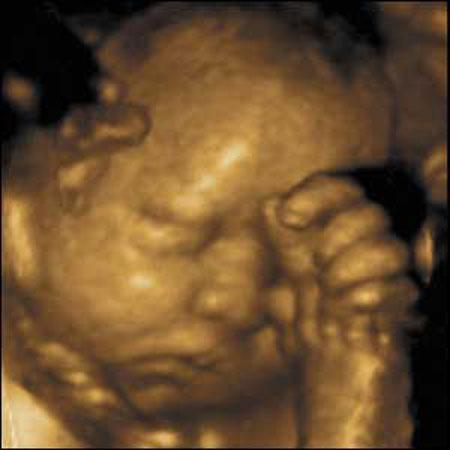

Ультразвуковые съёмки аборта на 12 неделе явно показывают: ребёнок чувствует боль, как любой из нас, и прекрасно понимает, что его хотят убить - он всеми силами старается отодвинуть от себя инструмент и широко раскрывает рот в безмолвном крике, когда у него отрывают сначала ноги, затем часть туловища…

Голову извлекают в последнюю очередь и лицо убитого ребёнка всегда искажено гримасой боли и ужаса. По этим кадрам видно, что практически нет разницы, убить ли 3-месячного ребёнка в утробе или отрезать руки -ноги -голову 5-летнему малышу. Без анестезии и в полном сознании.

- Фильм американского врача Бернарда Нэйтансона, названный «Безмолвный крик», показал всему миру, что такое аборт на сроке 11 недель беременности. Многие врачи и медсестры, посмотрев фильм, прекратили участвовать в абортах.

Это документальный фильм, и авторы рекомендуют соблюдать осторожность при его показе, поскольку некоторые кадры могут вызвать у человека психологический шок: безмолвный крик внутриутробного младенца, искаженное от боли лицо ребенка, погибающего на наших глазах...

Из закадрового текста к фильму: «Инструмент еще не коснулся ребенка, но он уже возбужден, его сердечные удары учащаются и достигают приблизительно 200 ударов в минуту. Вакуум-кюретка нащупывает ребенка, и он широко раскрывает рот в безмолвном крике».